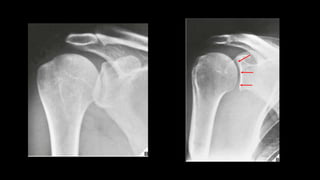

O documento aborda lesões no ombro, dividindo-as por faixas etárias: fraturas de clavícula em crianças, luxações em adultos e fraturas do úmero proximal em idosos. Descreve também técnicas de avaliação radiográfica e suas variações, incluindo incidências específicas para diagnóstico. Além disso, são mencionados métodos de imagem alternativos para a avaliação de partes moles e condições articulares.